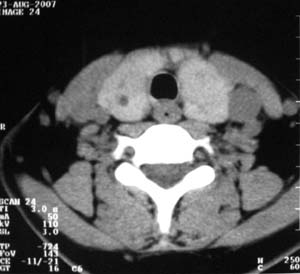

以下是引用zsl6918在2007-8-27 14:40:00的发言:[br]双侧甲状腺多发性低密度占位,边界清晰,密度欠均匀,尤以左侧明显,与周围组织分解清,考虑多发性腺瘤可能性大,不除外结节性甲状腺肿

以下是引用liaizhi在2007-8-27 15:20:00的发言:[br]双侧甲状腺散在多个囊性第密度影,左侧最大一个病灶与正常甲状腺分界尚可,气管受压稍右移。考虑甲状腺瘤的可能性大。